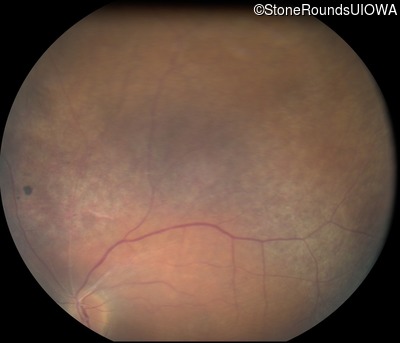

Fundus Photography - Right - 20/40 -2

Exemplar